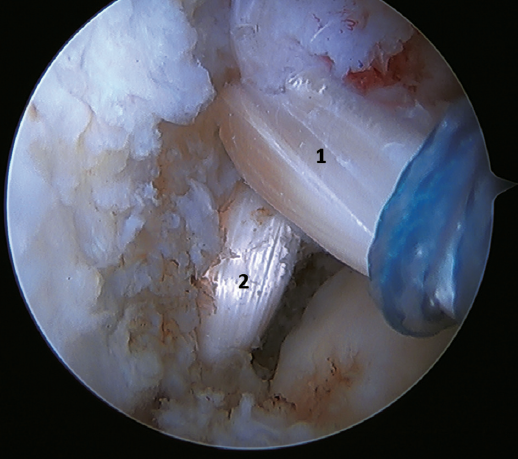

The techniques involving ATFL graft reconstruction via open surgery were described by Jeys(46) and Coughlin(47) in the early 2000s. Subsequently, and based on them, different arthroscopic techniques(48,49) have been described that restore joint stability with a low incidence of complications. These are the techniques of choice in cases of poor tissue quality, when ATFL rupture is at the talar insertion or in the mid-part of the ligament, in revision surgeries, and in patients with high functional demands, with hyperlaxity and/or a high body mass index (BMI).

These procedures are technically more demanding, although the development of biotenodesis-type implants and dynamic cortical anchorage systems has greatly facilitated their development and allows blind tunnels to be made, reducing neurovascular complications. Many different techniques and grafts have been described, each with potential advantages and disadvantages(24). Some studies on these techniques recommend resection of the ligament tissue remnant, as it poses a lesser risk of complications(50,51).

Another point of interest is the presence of os subfibulare. In these cases, we have the option of fixation, although this is usually not feasible and the best therapeutic option is excision and reconstruction, due to the impossibility of direct repair(60)(Figure 4).